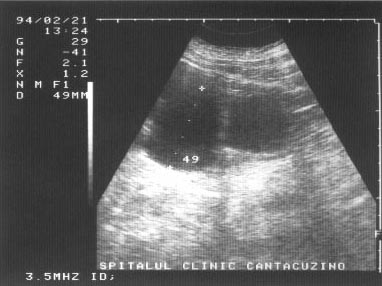

Figura 1. Vezica urinara

Figura 2. Chist renal stang situat in treimea medie

Figura 3. Chist ovar drept

Figura 4. Chist hepatic